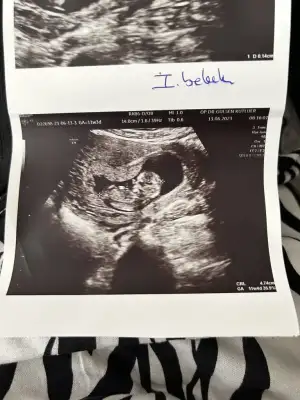

Maşallah sübhanallah her ay hamile kalabiliyorsunTıkabasa tarafından etiketlendiysem kesin bi iş vardır dıyenler el kaldırsın